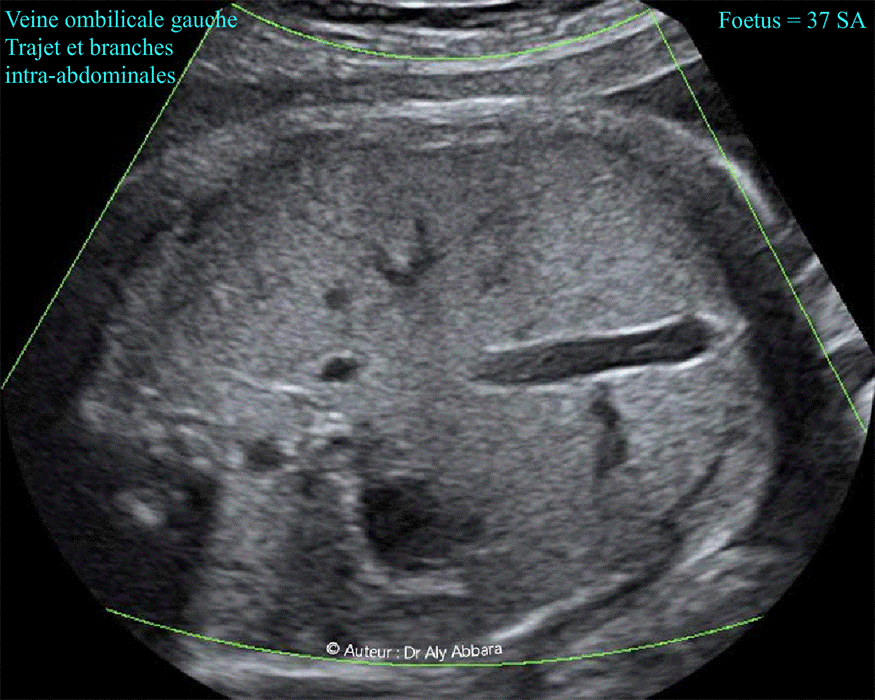

Veine ombilicale gauche normale - Son trajet intra-abdominal et ses branches

Images échographiques montrant une veine ombilicale gauche normale : son trajet et ses branches intra-abdominales.

La veine ombilicale (gauche) dessine une courbure à un angle de presque de 90° et à une convexité vers l'estomac.

Au niveau de son virage vers la droite (en direction du foie), la veine ombilicale donne une branche postérieure, c'est le canal veineux (conduit veineux ou ductus veineux) qui se dirige vers l'arrière pour se drainer directement dans la portion terminale sous-diaphragmatique de la veine cave inférieure, au même niveau du drainage des trois veines hépatiques.

La veine ombilicale, après avoir donné naissance au canal veineux, se dirige, sous le nom de " sinus porte " ou " processus portal ", vers le foie pour se diviser en plusieurs branches terminales intra-hépatiques (le plus souvent 3 branches).